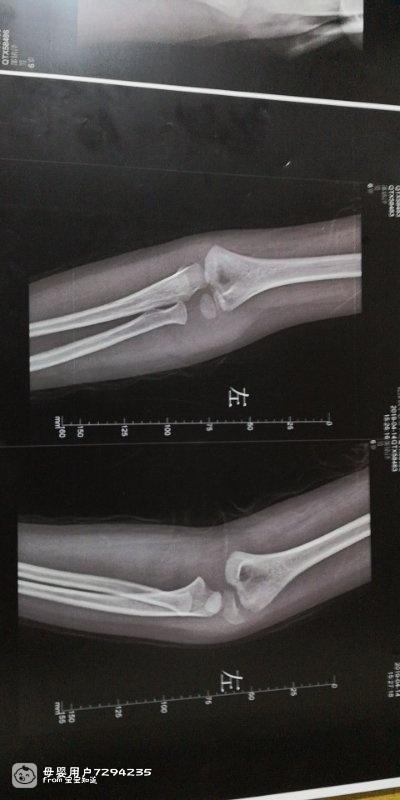

4岁小孩手肘断了怎么办

宝宝11岁7个月24天